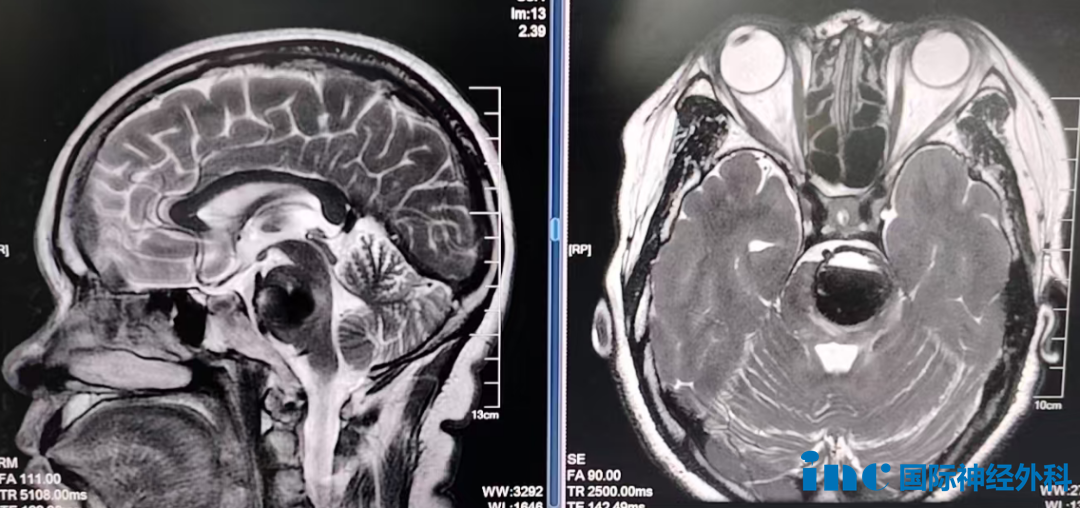

根据术前磁共振成像检查,50岁的方女士在过去六年期间,已经接受了多次开颅手术以及多次经鼻内镜手术,部分手术在美国多家知名医疗机构完成。由于手术次数较多,患者本人甚至难以记清具体次数,肿瘤病理分级也从最初的Ⅰ级进展为Ⅱ级。

肿瘤体积巨大,对垂体及垂体柄形成明显挤压,并且包绕了周围重要的血管与神经结构,这些结构包括颈内动脉、展神经、视神经以及动眼神经。肿瘤周边的血管壁异常脆弱,轻微触碰即存在破裂出血的风险。对于巴特朗菲教授这位国际神经外科权威专家来说,处理此类棘手情况已是临床常态。